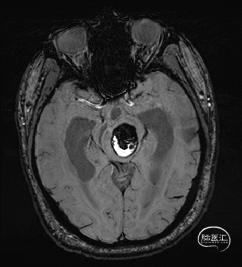

术前DTI检查

根据MRI及DTI显示,只有在丘脑与上丘之间的点(dot)进入病变才可能在切除病变时最大程度保护神经功能,由于上述原因,该“点”在术中显露极其困难,虽有导航指引,电生理监测的条件下,对术者的耐心、技术、经验及体能依然是极大的挑战;

术前详细的磁共振检查,包括平扫增强,SWI及DTI,可以规划出手术最适宜的路径及切入点;